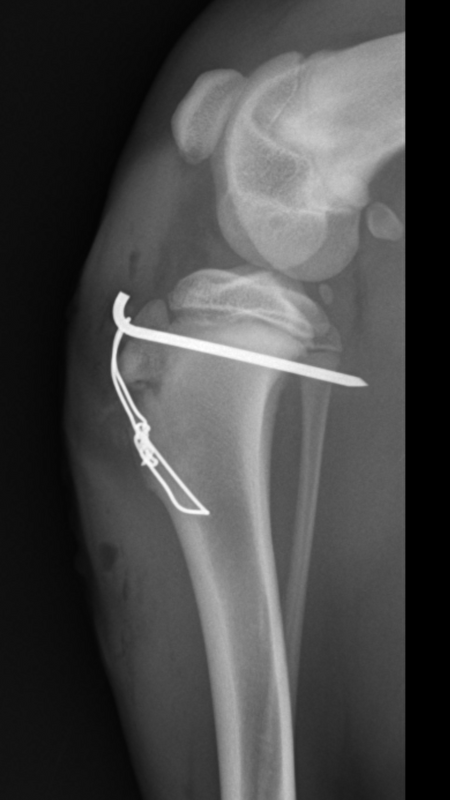

Ze hebben tijdens de operatie een ijzeren pin er in gezet met een stuk ijzerdraad, die het bot weer op z'n plek moet houden.

Met 4 week moeten we weer een röntgenfoto laten maken hoe het bot er uit ziet,en dan een afspraak maken om de pin weer operatief te laten verwijderen.

Zo ziet z'n poot er nu uit: